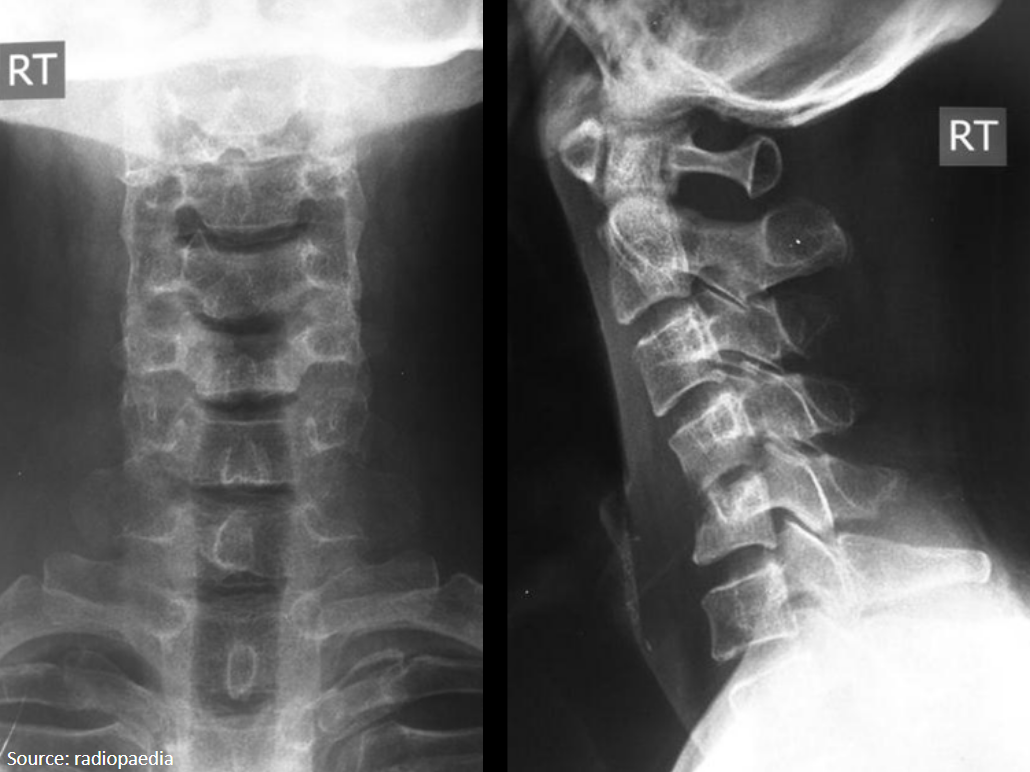

21

Q

What is seen on these radiographs that suggests spondylodiscitis?

A

Paraspinal abscess on AP

Endplate erosive changes on lateral

cold abscess in psoas